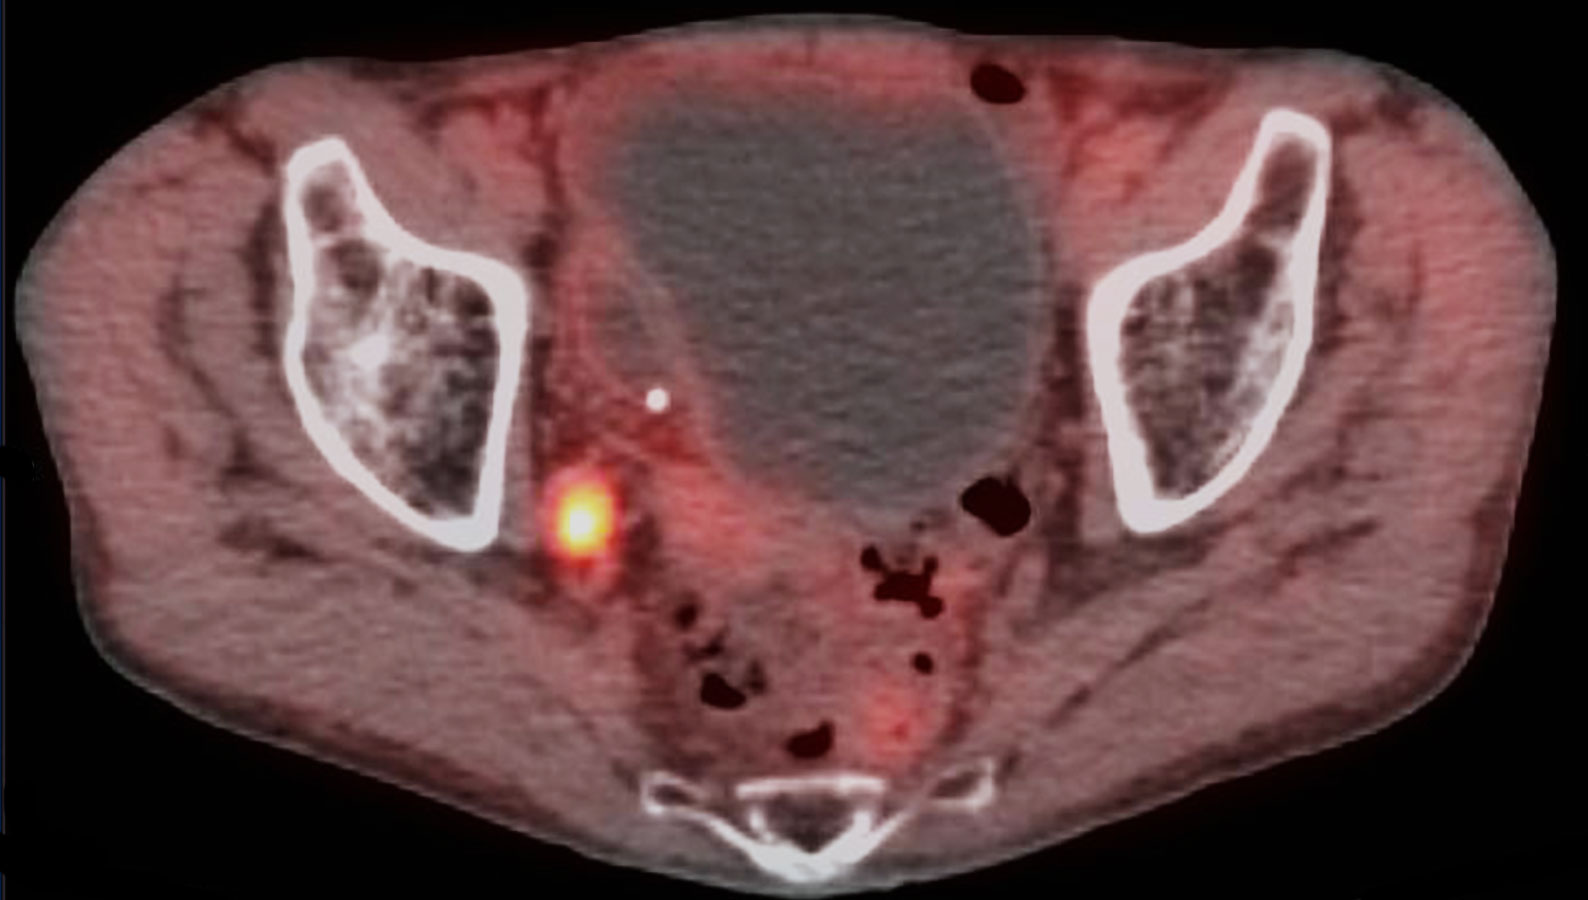

Unlike bone scan which only shows osteoblastic process Axumin PET shows both bony and soft tissue lesions indicative of tumor cellular proliferation. Axumin is indicated for positron emission tomography PET in men with suspected prostate cancer recurrence based on elevated blood prostate specific antigen PSA.

Ad Read About The Impact Of Axumin PETCT Imaging On Clinical Management. Axumin fluciclovine F 18 injection is indicated for positron emission tomography PET imaging in men with suspected prostate cancer recurrence based on elevated blood prostate. Indications and Usage for Axumin Axumin is indicated for positron emission tomography PET in men with suspected prostate cancer recurrence based on elevated blood.

Ad Read About The Impact Of Axumin PETCT Imaging On Clinical Management. Ad Learn About Imaging Scans and Questions You Can Ask Your Doctor About Scans. Axumin is indicated for Positron Emission Tomography Computed Tomography PETCT imaging in men with suspected prostate cancer recurrence based on elevated blood.